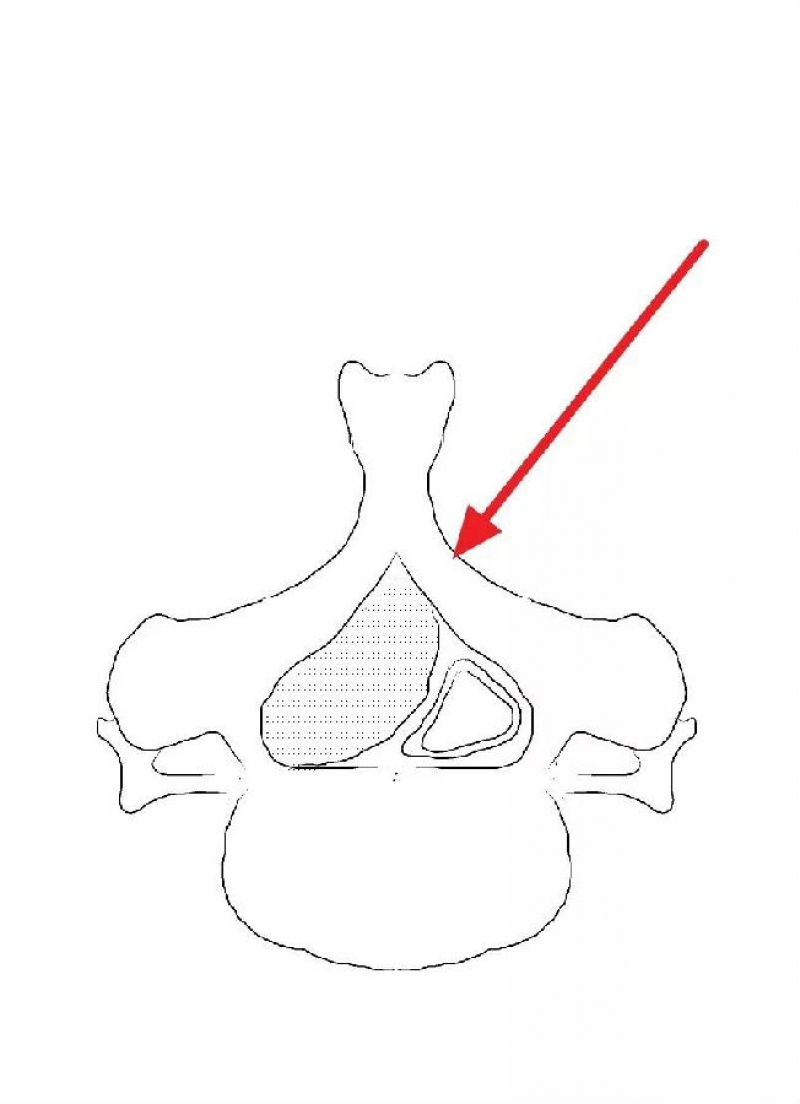

颈椎内镜下单侧入路双侧减压(ULBD)中,减压的难点还是在于识别棘突与椎板的移行部位及对侧结构的显露。

临床上,0°镜子绝对是颈椎UBE的最好用的镜子,但是30°的镜子对侧中线结构的显露及对侧结构的显露具有更广角的视野。在进行同侧减压之前,中线结构的显露是关键。

1. 术中如何确定中线?

2. 术中骨赘的界限?

3. 如何确定对侧结构?

4. 如何确定减压范围?